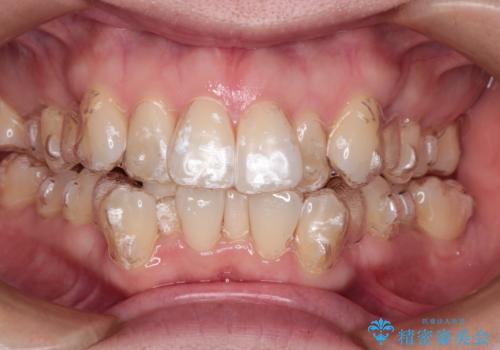

【抜歯ケース】前歯のガタガタをインビザラインで治療

- 矯正装置

- インビザライン

- 治療期間

- 2年6ヶ月

- 前歯のガタガタを主訴に来院されました。

抜歯が必要なケースでしたが、インビザラインでの治療を希望されワイヤーを使用せずに治療を完了しております。